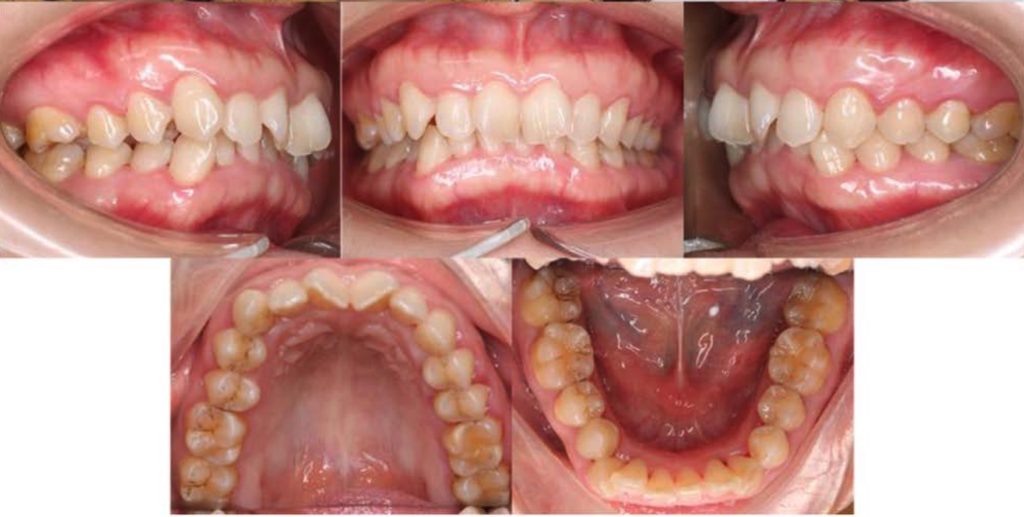

El artículo trata sobre un reporte de caso clínico que describe el diagnóstico y manejo ortodóntico de una paciente adulta con una maloclusión de Clase II división 2 (unilateral) con mordida profunda y desviación de la línea media. El caso se manejó con un protocolo de extracción asimétrica de 3 premolares: ambos primeros premolares maxilares y el segundo premolar mandibular en el lado de la Clase II.

Los autores concluyen que para casos seleccionados de Clase II subdivisión en adultos, la extracción asimétrica de 3 premolares es una alternativa predecible y que minimiza la dependencia de la colaboración del paciente (a diferencia de las extracciones simétricas de 4 premolares que requieren elásticos Clase II).